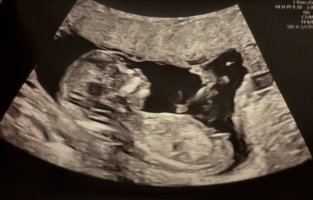

Veldig utydelig NUB, men tipper guttVis vedlegget 474235

Noen som vil gjette?

TIpper guttVis vedlegget 474235